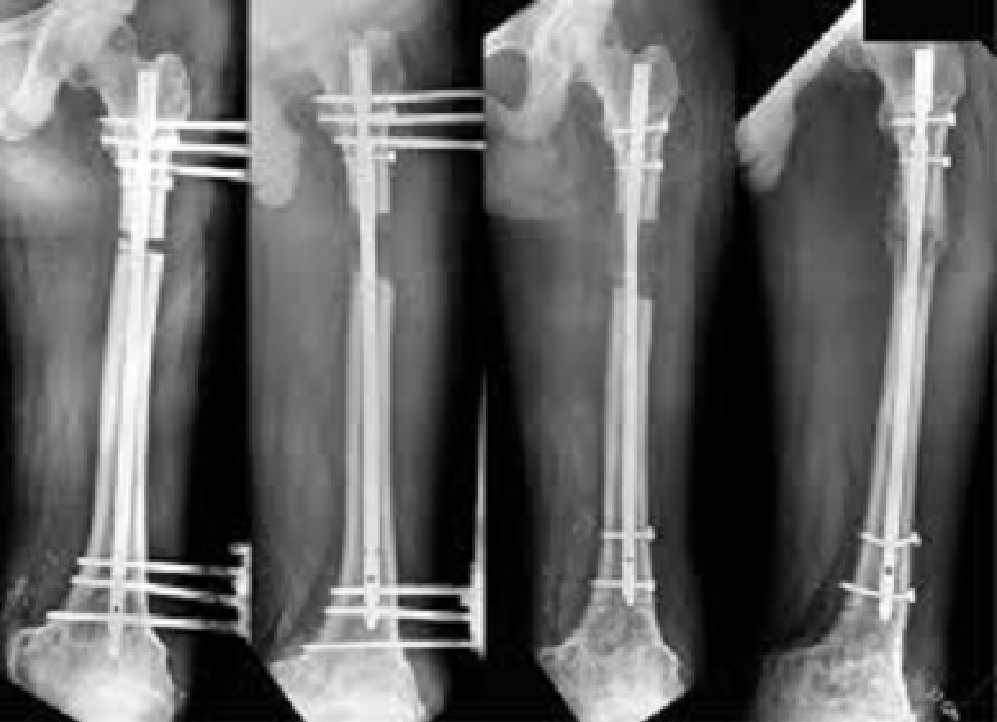

LON (lengthening over nail)

Dr.Jijeesh